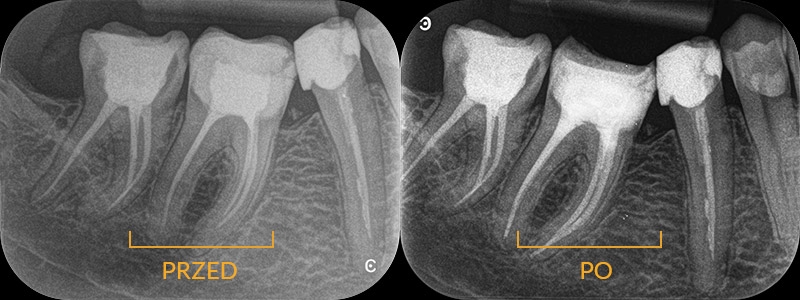

Złamane narzędzie w kanale zęba

Pacjent leczony poza naszą kliniką zgłasza się z bólem. Zdjęcie wykazuje zmiany zapalne okołokorzeniowe, a także pozostawione w kanale złamane narzędzie (pilnik), które uniemożliwia jego opracowanie. Tylko w powiększeniu mikroskopu lekarz jest w stanie usunąć przeszkodę i opracować kanał do końca. Nasza endodontka przystępuje do pracy, usuwając najpierw narzędzie, potem wykonując powtórne leczenie kanałowe. Kontrolne zdjęcie wykazuje prawidłowe wypełnienie kanałów, a także gojenie zmiany zapalnej.